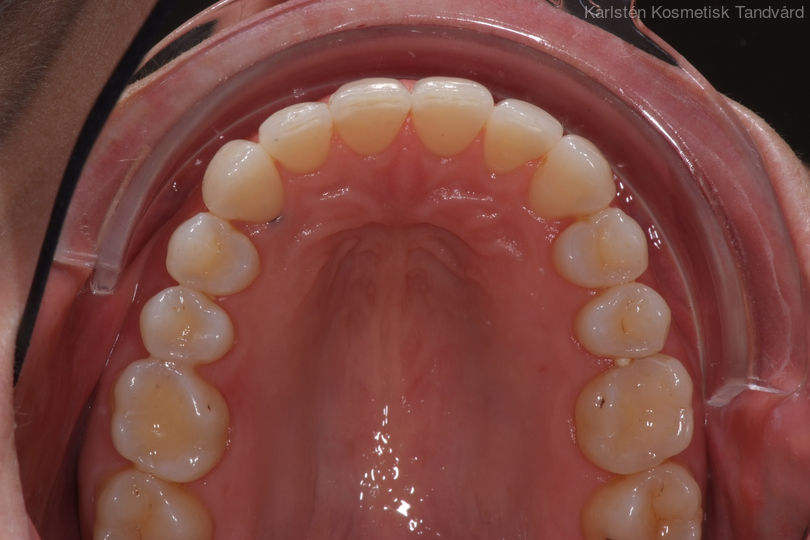

Tandreglering 5

32-årig kvinna som tycker att hon bara visar sina framtänder. En utjämning och vidgning av tandbågen med 8 månaders genomskinliga Invisalignskenor, gav henne ett fint leende.